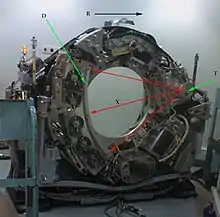

Mechanism

T: X-ray tube

D: X-ray detectors

X: X-ray beam

R: Gantry rotation

Computed tomography operates by using an X-ray generator that rotates around the object; X-ray detectors are positioned on the opposite side of the circle from the X-ray source.[199] As the X-rays pass through the patient, they are attenuated differently by various tissues according to the tissue density.[200] A visual representation of the raw data obtained is called a sinogram, yet it is not sufficient for interpretation.[201] Once the scan data has been acquired, the data must be processed using a form of tomographic reconstruction, which produces a series of cross-sectional images.[202] These cross-sectional images are made up of small units of pixels or voxels.[203]